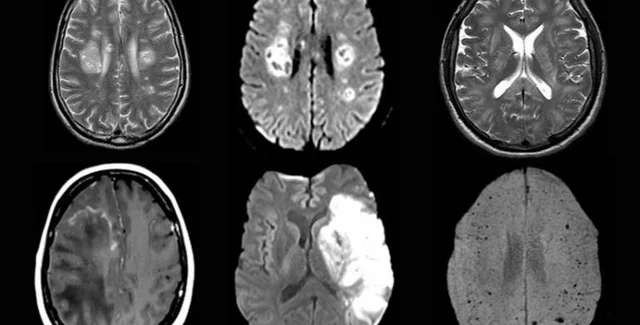

Фото: UCL

Они изучили протекание болезни у 43 человек в возрасте от 16 до 85 лет. У 10 из них была выявлена временная дисфункция мозга, а у 12 — его воспаления, некоторые из которых являлись острым диссеминированным энцефаломиелитом. Также наблюдались другие серьезные повреждения, например инсульты.

При этом вирус SARS-CoV-2, вызывающий COVID-19, не был обнаружен в мозговой жидкости ни у одного из протестированных пациентов. Это позволяет предположить, что вирус непосредственно не воздействовал на мозг, вызывая неврологическое заболевание. Необходимы дальнейшие исследования, чтобы определить, почему же у пациентов развивались эти осложнения.

У некоторых пациентов исследователи обнаружили указания на то, что воспаление мозга, вероятно, было вызвано иммунным ответом организма на заболевание.